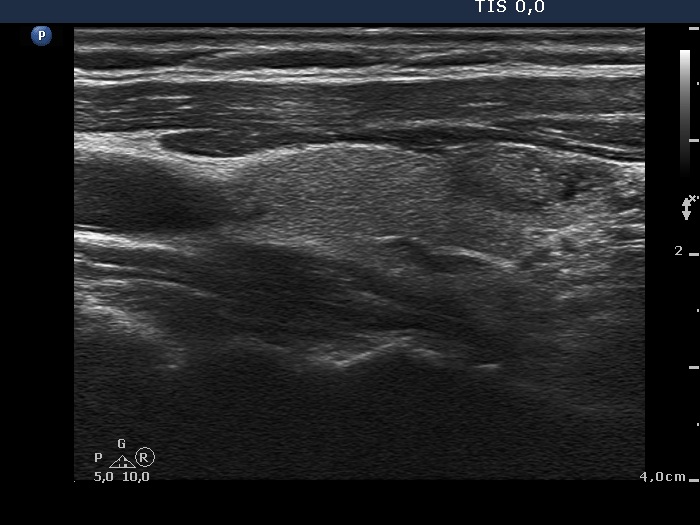

Ultrasonography. The thyroid was echonormal. There was a minimally-moderately hypoechogenic nodule in the right while a cystic nodule in the left lobe. There were numerous hyperechogenic figures both in the cystic and in the lower solid part of the lesion. The lesion presented no vascularization.

Comment. The presentation of the bright hyperechogenic granules are relatively unusual, they were mostly located within the solid part causing a false impression of starry sky phenomenon. In fact, they were comet-tail artifacts.